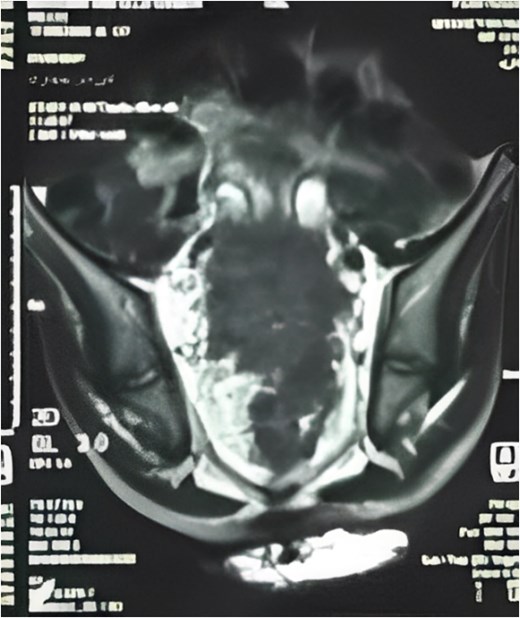

Subsequently, he underwent open low anterior resection with primary colorectal anastomosis, diverting loop ileostomy, and en bloc resection of both ureters. Due to a concurrent urinary tract infection, urinary reconstruction was deferred. The right ureter remained intact, but the left ureter was involved with the tumor and required resection. The resected specimen (Fig. 3) revealed moderately differentiated adenocarcinoma with clear margins, and all six regional lymph nodes were negative for tumor infiltration (pT4a pN0 M0).

Total mesorectal excision (TME) specimen, with arrow pointing to the tumor.